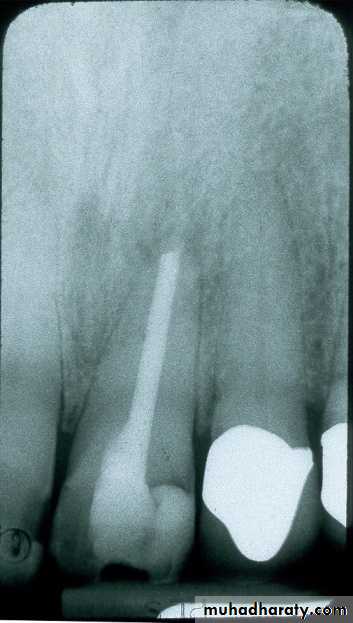

Some patients, especially larger individuals, will have longer than normal teeth. With the normal positioning of the film and alignment of the beam, the apices of the teeth will be above the edge of the film (not visible or “cut off”) as in the illustration above left.

To compensate for this, increase the angle of the beam and raise the PID slightly (illustration above right). You are purposely foreshortening the image.

top edge of PID above ring